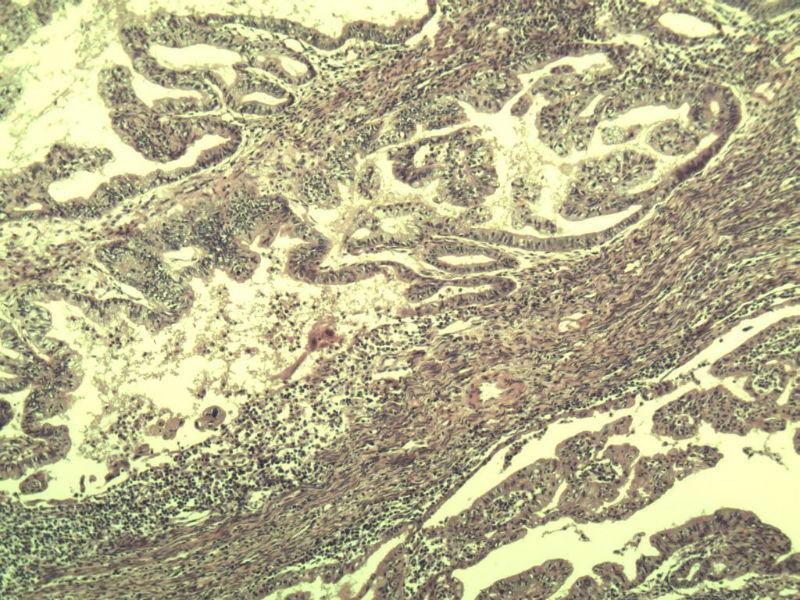

女,57岁,全切子宫一个,宫体体积 9 × 8 × 7 cm3,肌壁厚 2.5 cm,内膜菲薄,部分区域增厚达 0.4 cm(约3*2.5cm区域)。 请问各位老师  这个可以诊断子宫内膜癌了吧?      深肌层没有看到浸润。

患者因"发现下腹部包块1月多"入院  宫体体积 9 × 8 × 7 cm3,肌壁厚 2.5 cm,内膜菲薄,部分区域厚 0.4 cm(约3*2.5cm)。宫颈结构不清,长约 2.5 cm,表面欠光滑。临床诊断宫颈宫腔积液.

宫内膜样腺癌

筛状、迷路样结构

间质消失或者纤维性间质

子宫内膜样腺癌

高分化子宫内膜样癌。浸润浅肌层(深度<1/3肌层)。根据FIGO2009分期,子宫内膜癌局限于内膜层和<1/2肌层,都属于IA期。二者处理不再区别对待。